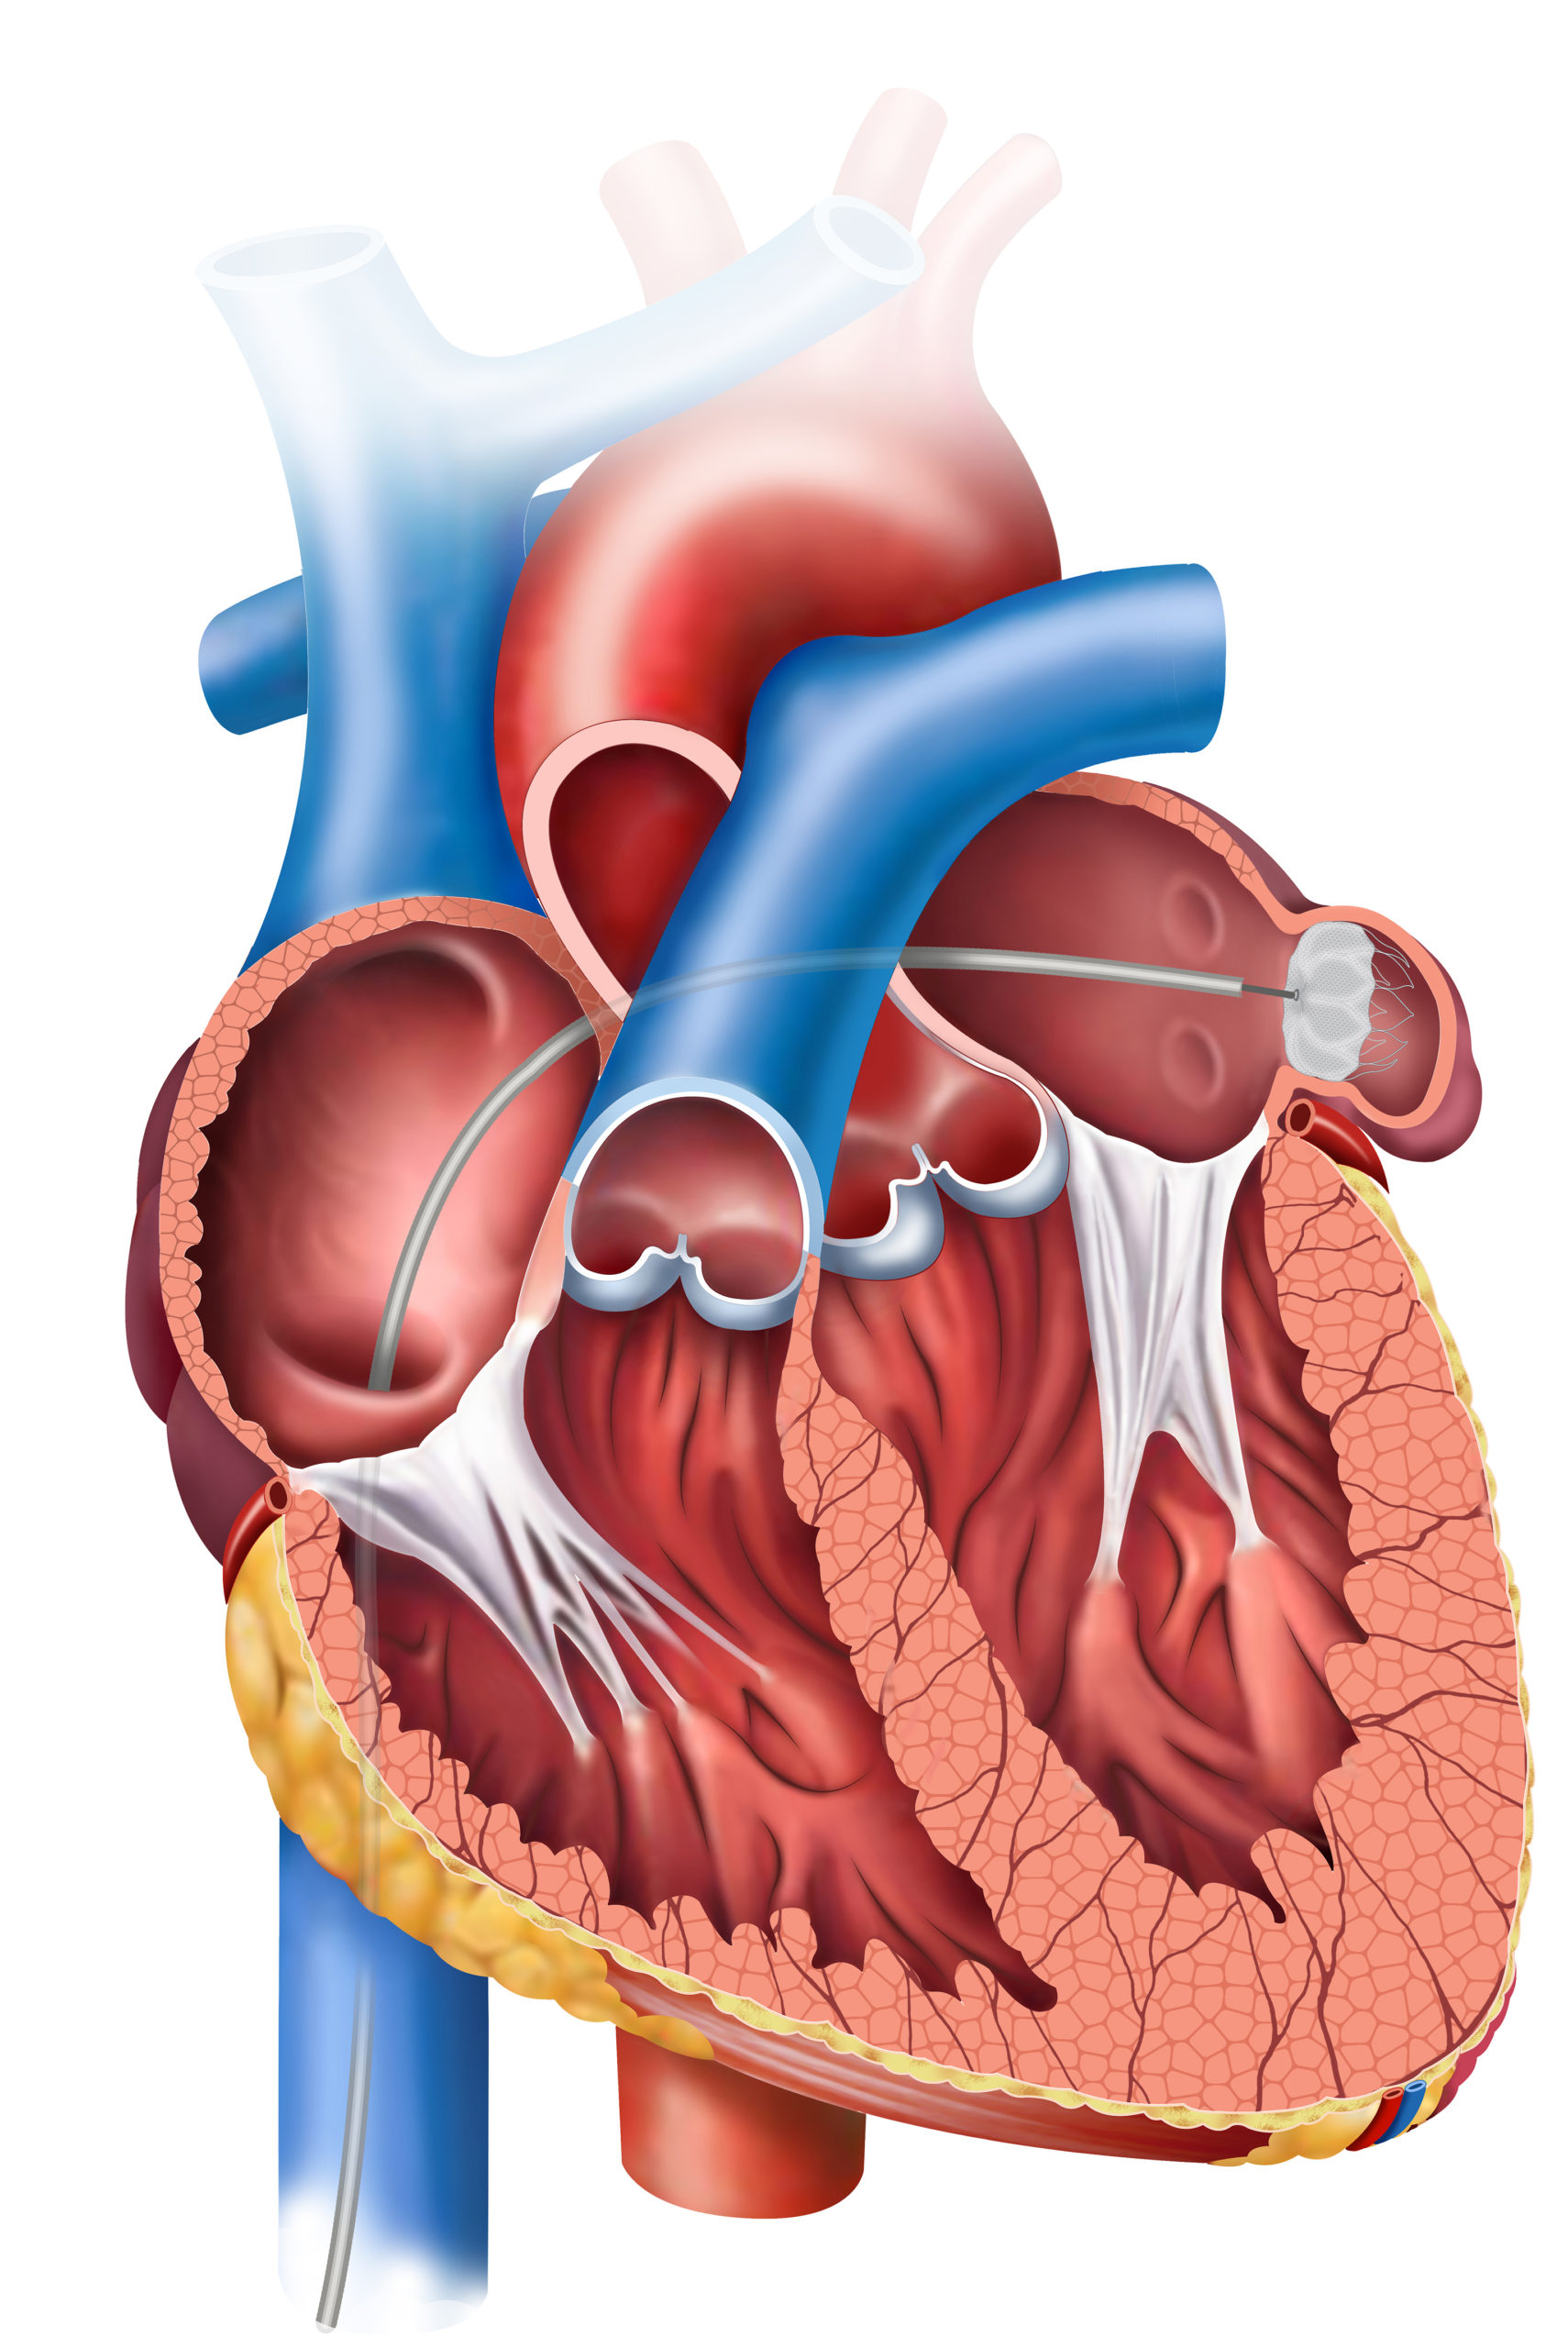

Holographic Therapy Guidance (HTG) is a new technology developed by EchoPixel that generates a real-time digital ...Patrick DalyAtrial Fibrillation | April 7, 2023